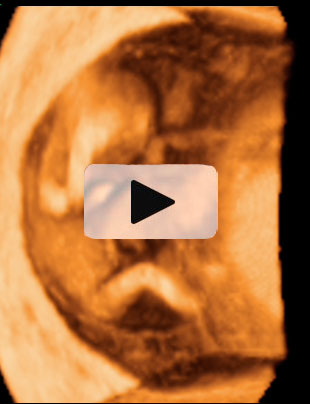

Ecografía 4D de la semana 12: Feto mirando "a la cámara"

Esta ecografía 4D muestra a un bebé de 12 semanas de gestación que se encuentra situado contra la pared del útero materno. El feto parece mirar varias veces hacia el ecógrafo y se tapa la cara con los brazos. Puede observarse con gran detalle la estructura ósea de la mano.

Ecografía en 4D de un feto de 12 semanas "mirando a la cámara"

A este niño de 12 semanas de gestación parece que le ha "pillado" el ecógrafo desprevenido y se quiere esconder. El bebé está contra la pared uterina: se da cuenta de que el ecografista le está "enfocando" y parece con si se quisiera esconder del público, como las estrellas de cine. Mira varias varias veces "a cámara", en una actitud sorprendente; se tapa la cara con los brazos. La mano se perfila perfectamente, así como muchas de sus estructuras óseas, mientras se esconde cara a la pared uterina.